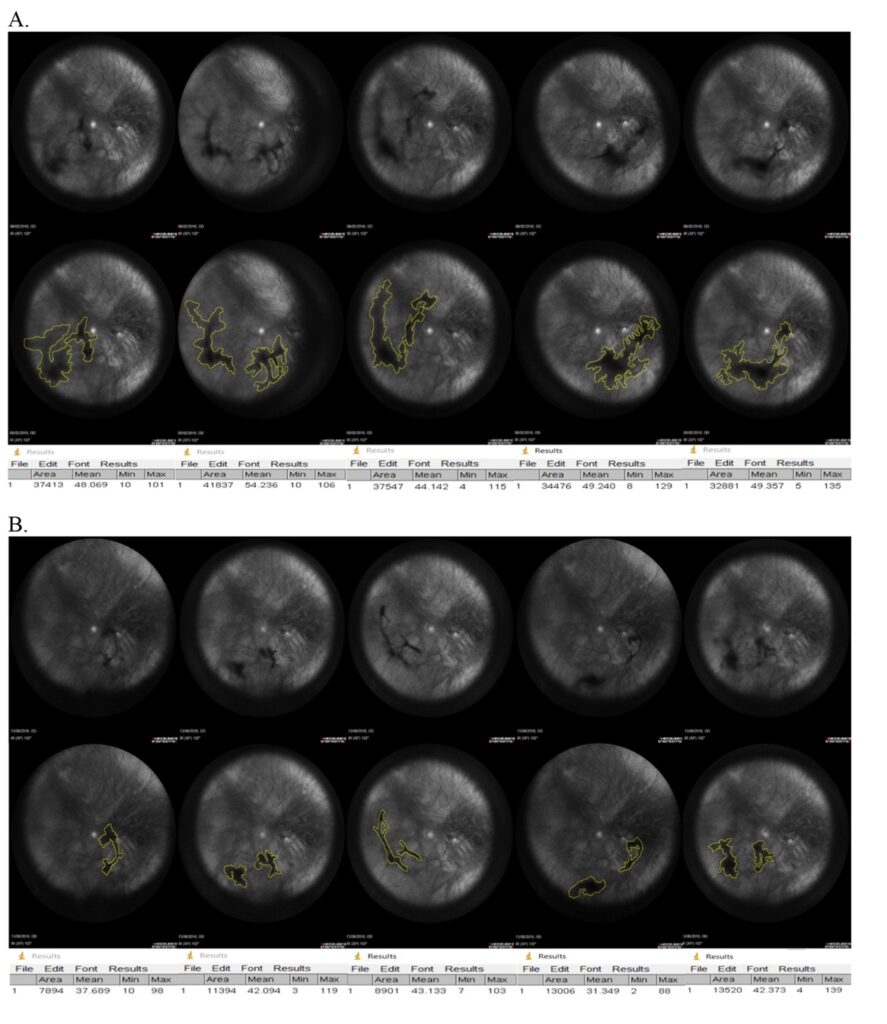

De FLIES-studie is de eerste in zijn soort die het effect van gerichte voedingssupplementen op mouches volantes onderzocht in een gerandomiseerde, dubbelblinde, placebo-gecontroleerde klinische studie. Aan het onderzoek namen 61 patiënten deel in de leeftijdscategorie van 18 tot 79 jaar, die gedurende zes maanden dagelijks VitroCap®N of een placebo innamen. De evaluatie vond plaats aan de hand van de volgende meetmethoden:

Resultaten: In het onderzoek werden significante verbeteringen aangetoond in zowel subjectieve visuele klachten als objectieve parameters.

2. Bij 77% van de patiënten werd een vermindering van de omvang van de glasvochttroebeling vastgesteld.

De klinische studie werd uitgevoerd bij 32 patiënten van 37 tot 57 jaar, bij wie door middel van oogechografie glasvochttroebelingen waren vastgesteld. De patiënten werden in twee groepen verdeeld: 16 patiënten met symptomatische mouches volantes kregen gedurende drie maanden VitroCap®, de andere 16 (zonder visuele klachten door hun floaters) werden niet behandeld.

Resultaten: In het onderzoek werden significante verbeteringen aangetoond in zowel subjectieve visuele klachten (vragenlijst) als objectieve parameters (oogechografie) na de behandeling met VitroCap®.

De observaties bevestigden dat het gebruik van VitroCap® het visuele comfort verbetert en in de meeste gevallen de subjectieve klachten van patiënten over mouches volantes vermindert. Bovendien was er een zichtbare trend naar een afname van de glasvochttroebelingen en een verbetering van hun kwalitatieve eigenschappen.